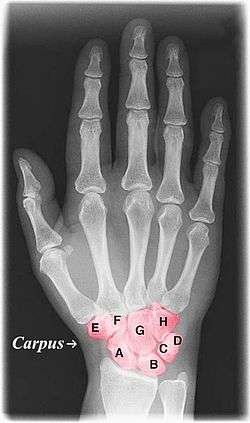

The carpal bones are the eight small bones that make up the wrist (or carpus) that connects the hand to the forearm. This term derives its meaning from the Latin carpus and the Greek καρπός (karpós), both meaning "wrist." In human anatomy, the main role of the wrist is to facilitate effective positioning of the hand and powerful use of the extensors and flexors of the forearm, and the mobility of individual carpal bones increase the freedom of movements at the wrist.[1]

In human anatomy, there are 8 carpal bones which can be classified as either belonging to two transverse rows, or three longitudinal columns.

Position of carpal bones (shown in red). Animation.